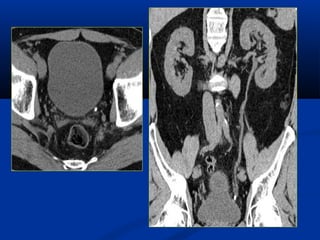

THAY ÑOÅI HÌNHAÛNH -Trò soá ñaäm ñoä cuûa caùc moâ cô theå thay ñoåi töø –1000HU ñeán +1000 HU -Bieåu hieän treân hình baèng caùc ñoä xaùm khaùc nhau. -Tuy nhieân maét thöôøng cuûa chuùng ta chæ phaân bieät ñöôïc töø 15 – 20 ñoä xaùm khaùc nhau. Do ñoù ñeå coù theå phaân bieät ñöôïc caùc caáu truùc khaùc nhau ñaët cöûa soå (Window setting ) taïo töông phaûn giuùp maét thöôøng ta nhaän bieát ñöôïc.

ÑOÄ ROÄNG CÖÛASOÅ (WINDOW WIDTH) -Giôùi haïn treân vaø giôùi haïn döôùi cuûa trò soá ñaäm ñoä caàn khaûo saùt . - Trò soá ñaäm ñoä ngoaøi giôùi haïn treân seõ coù maøu traéng treân hình, caùc trò soá ñaäm ñoä

TRUNG TAÂM CÖÛASOÅ ( WINDOW LEVEL ) Trò soá giöõa cuûa ñoä roäng cöõa soå Ñieàu chænh cho phuø hôïp vôùi toå chöùc moâ caàn khaûo saùt